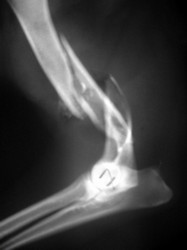

PRÁCTICAS CURSO DE FIJACIÓN EXTERNA PERFECCIONAMIENTO.

Húmero.